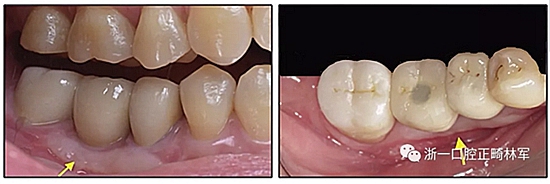

36歲;女性;尋求下頜左后方區(qū)域間隙管理的建議(圖1和圖2),通過(guò)治療獲得了良好的牙頜面效果(圖3和圖4)。她被診斷患有骨性I類(lèi)和代償性牙性II類(lèi)錯(cuò)合畸形,并且上頜左側(cè)尖牙缺失(圖1和2)。大約七年前,由于不可修復(fù)的齲齒,拔除了下頜左側(cè)第一和第二磨牙(圖5)。37相鄰的第三磨牙向近中移動(dòng)并傾斜入間隙,導(dǎo)致無(wú)牙頜間隙減小至約14 mm(圖2和圖5)。臨床和影像學(xué)評(píng)估顯示多發(fā)性齲損和在下頜右側(cè)567處有一不良的固定橋修復(fù)體(圖1和5)。此外,下頜左中切牙缺失,造成下頜中線(xiàn)向左側(cè)偏移約3 mm(圖1和圖2)?;颊咦栽V,她的右上第一前磨牙和左上尖牙在13歲時(shí)由其家庭牙醫(yī)拔除,因?yàn)樗鼈儽蛔枞筋a側(cè)萌出(圖1)。上頜第二磨牙缺失(未知病因),并且相鄰的第三磨牙已經(jīng)轉(zhuǎn)移到第二磨牙間隙中。如補(bǔ)充材料所示,美國(guó)正畸學(xué)差異指數(shù)DI是28分。種植體部位(下頜左側(cè)和右側(cè)第一磨牙)由于復(fù)雜性得到額外4分(補(bǔ)充材料)。

圖2. 治療前牙齒模型